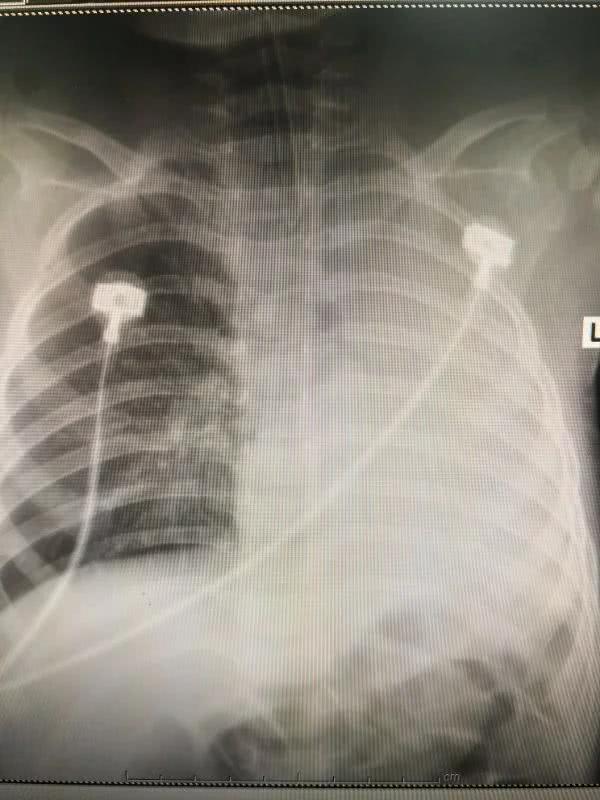

正写着病历的值班大夫叶碧波听见声响,急忙站起身,而此时一行人已经冲进了这间办公室。“当时马上检查了孩子的情况,不太好。”叶碧波称,小雨当时精神差,且出现烦躁、面色发绀、呼吸急促费力、三凹征阳性、心率快、左肺呼吸消失、右肺较多湿啰音等情况,这样的种种表现都反映一个问题,“孩子病情危重,得先转监护室治疗。”

在查了胸部CT后,上述医院的大夫告诉小雨父母,孩子的左主支气管异物堵塞、左肺不张、右肺肺炎,他们医院处理不了,“推荐我们赶快到郑大三附院看。”小雨的家人说道。